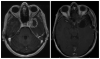

Object: Glioblastoma is the most aggressive and diffusely infiltrative primary brain tumor. Recurrence is expected and is extremely difficult to treat. Over the past decade, the accumulation of knowledge regarding the molecular and genetic profile of glioblastoma has led to numerous molecularly targeted therapies. This article aims to review the literature and highlight the mechanisms and efficacies of molecularly targeted therapies for recurrent glioblastoma.

Results: A total of 42 articles were included in this review. In the treatment of recurrent glioblastoma, various targeted therapies have been tested over the past 10-15 years. The targets of interest include epidermal growth factor receptor, vascular endothelial growth factor receptor, platelet-derived growth factor receptor, Ras pathway, protein kinase C, mammalian target of rapamycin, histone acetylation, and integrins. Unfortunately, the clinical responses to most available targeted therapies are modest at best. Radiographic responses generally range in the realm of 5%-20%. Progression-free survival at 6 months and overall survival were also modest with the majority of studies reporting a 10%-20% 6-month progression-free survival and 5- to 8-month overall survival. There have been several clinical trials evaluating the use of combination therapy for molecularly targeted treatments. In general, the outcomes for combination therapy tend to be superior to single-agent therapy, regardless of the specific agent studied.

Conclusions: Recurrent glioblastoma remains very difficult to treat, even with molecular targeted therapies and anticancer agents. The currently available targeted therapy regimens have poor to modest activity against recurrent glioblastoma. As newer agents are actively being developed, combination regimens have provided the most promising results for improving outcomes. Targeted therapies matched to molecular profiles of individual tumors are predicted to be a critical component necessary for improving efficacy in future trials.